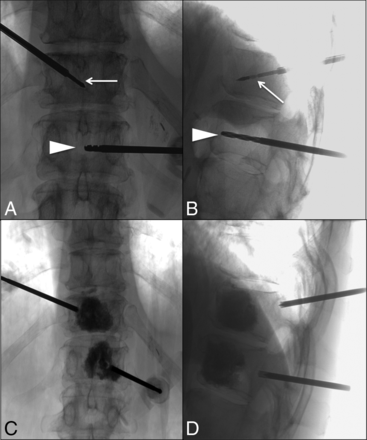

Subsequently, a single 14- or 16-g Avecure microwave ablation antenna (MedWaves, 1.8-mm, 20-cm-long) was coaxially inserted into the tumor. Placement of the hand drill and the ablation antenna is demonstrated in Fig 2. The size of the ablation antenna was determined on the basis of the calculated target lesion size, with the ablation zone calculated as 2 mm beyond the actual size of the target lesion to achieve adequate control. To calculate the appropriate cutoff temperature and energy deposition, we took the following approach: anteroposterior, lateral, and transverse measurements of the probe position relative to the vertebral margins. These measurements were then used to determine the appropriately sized antenna. Energy in kilojoules and temperature in centigrade were subsequently calculated using the vendor's standard algorithm. The team was then able to achieve these end points with our ablation.

Intraprocedural anteroposterior (A) and lateral (B) fluoroscopic images of T11- and T12-level microwave ablation. A microwave ablation probe (arrow) and a manual drill (arrowhead) have been advanced through access cannulas into the anterior aspect of the T11 and T12 vertebral bodies, respectively. Anteroposterior (C) and lateral (D) fluoroscopic images of the T11 and T12 vertebral bodies post-microwave ablation and cement augmentation. The access cannulas have been retracted into the pedicles.